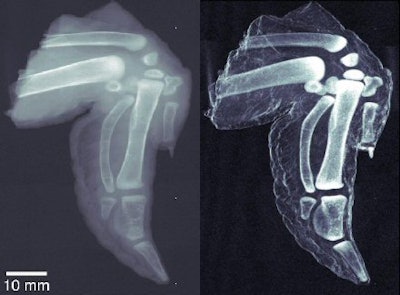

The images the group has produced so far indicate sharply higher image quality for dark-field x-rays when compared to images produced with conventional absorption-based techniques. Pfeiffer said the difference isn't so much higher spatial resolution for the dark-field technique; rather, certain types of structures -- such as very small cracks or abrupt edges -- produce scatter radiation that shows up well on dark-field images.

This means that a dark-field x-ray system could be adept at detecting small hairline fractures that might not be visible on a conventional digital x-ray unit. Another promising application could be bone density measurement.

Despite its promise, dark-field x-ray could be a ways from your local hospital or imaging center. The closest thing to a human the researchers have studied was a chicken wing purchased from a local grocery store. But the group is in the process of getting regulatory approval for studying human subjects, and Pfeiffer estimates that such trials could be about a year away.

| At left, conventional radiography image of chicken wing. At right, dark-field x-ray image of same chicken wing. Images courtesy of Franz Pfeiffer, Ph.D. |